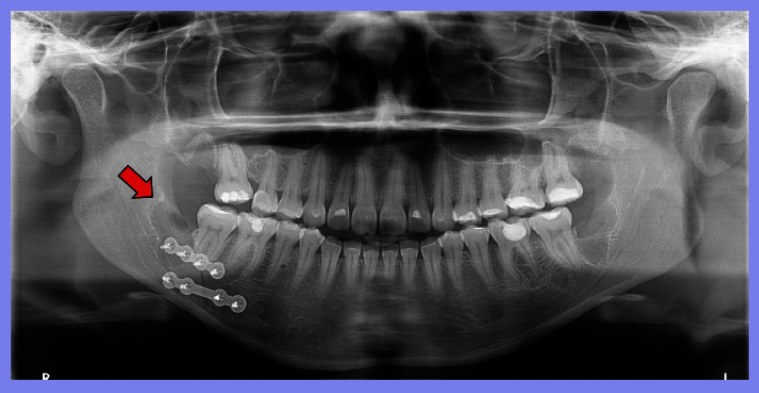

在医院对患者进行检查,除全身健康状况外,临床评估还显示右侧面部剧烈疼痛和肿胀、下颌轮廓明显凹陷、张口受限、咬合不正、前段骨性活动性差、右下颌第三磨牙缺失。计算机断层扫描 (CT) 扫描和 3D 重建分别显示直角部位下颌节段的牙槽骨连续性断裂和横向移位的髁突 (远端) 碎片。水肿消退后,在全身麻醉下进行下颌骨骨折治疗。外科医生进行口内切开复位,重新定位节段,并使用两块钛板和六毫米螺钉防止碎片移动并确保骨一期愈合。在同一手术中,对侧上下第三磨牙也被拔除。

术后给予止痛药和抗炎药。在接下来的几个月中,观察到第三磨牙对应区域的骨重建令人满意,咬合恢复。手术和术后恢复都很顺利。